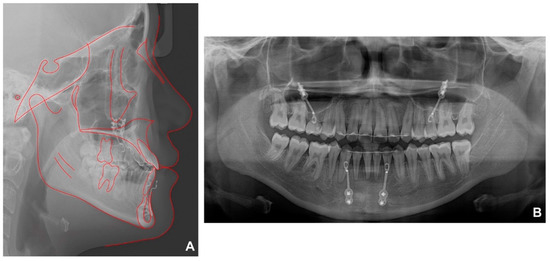

After 39 months of secondary orthodontic treatment, all spaces were closed, the anterior crossbite and lateral open bite improved, and stable occlusion was achieved (Figure 6). After treatment, most cephalometric values, except SNA, improved within the normal range (Figure 7A, Table 1). Panoramic radiography demonstrated that the mandibular right third molar erupted in an upright position (Figure 7B). No significant root resorption was observed in the maxillary anterior teeth, but the periodontal ligament was clearly widened. It was observed that the right maxillary sinus pneumatization was severe up to the place where the impacted tooth was in the past.

Figure 7. Radiographs after debonding: (A) lateral cephalometric radiographs; (B) panoramic radiograph.